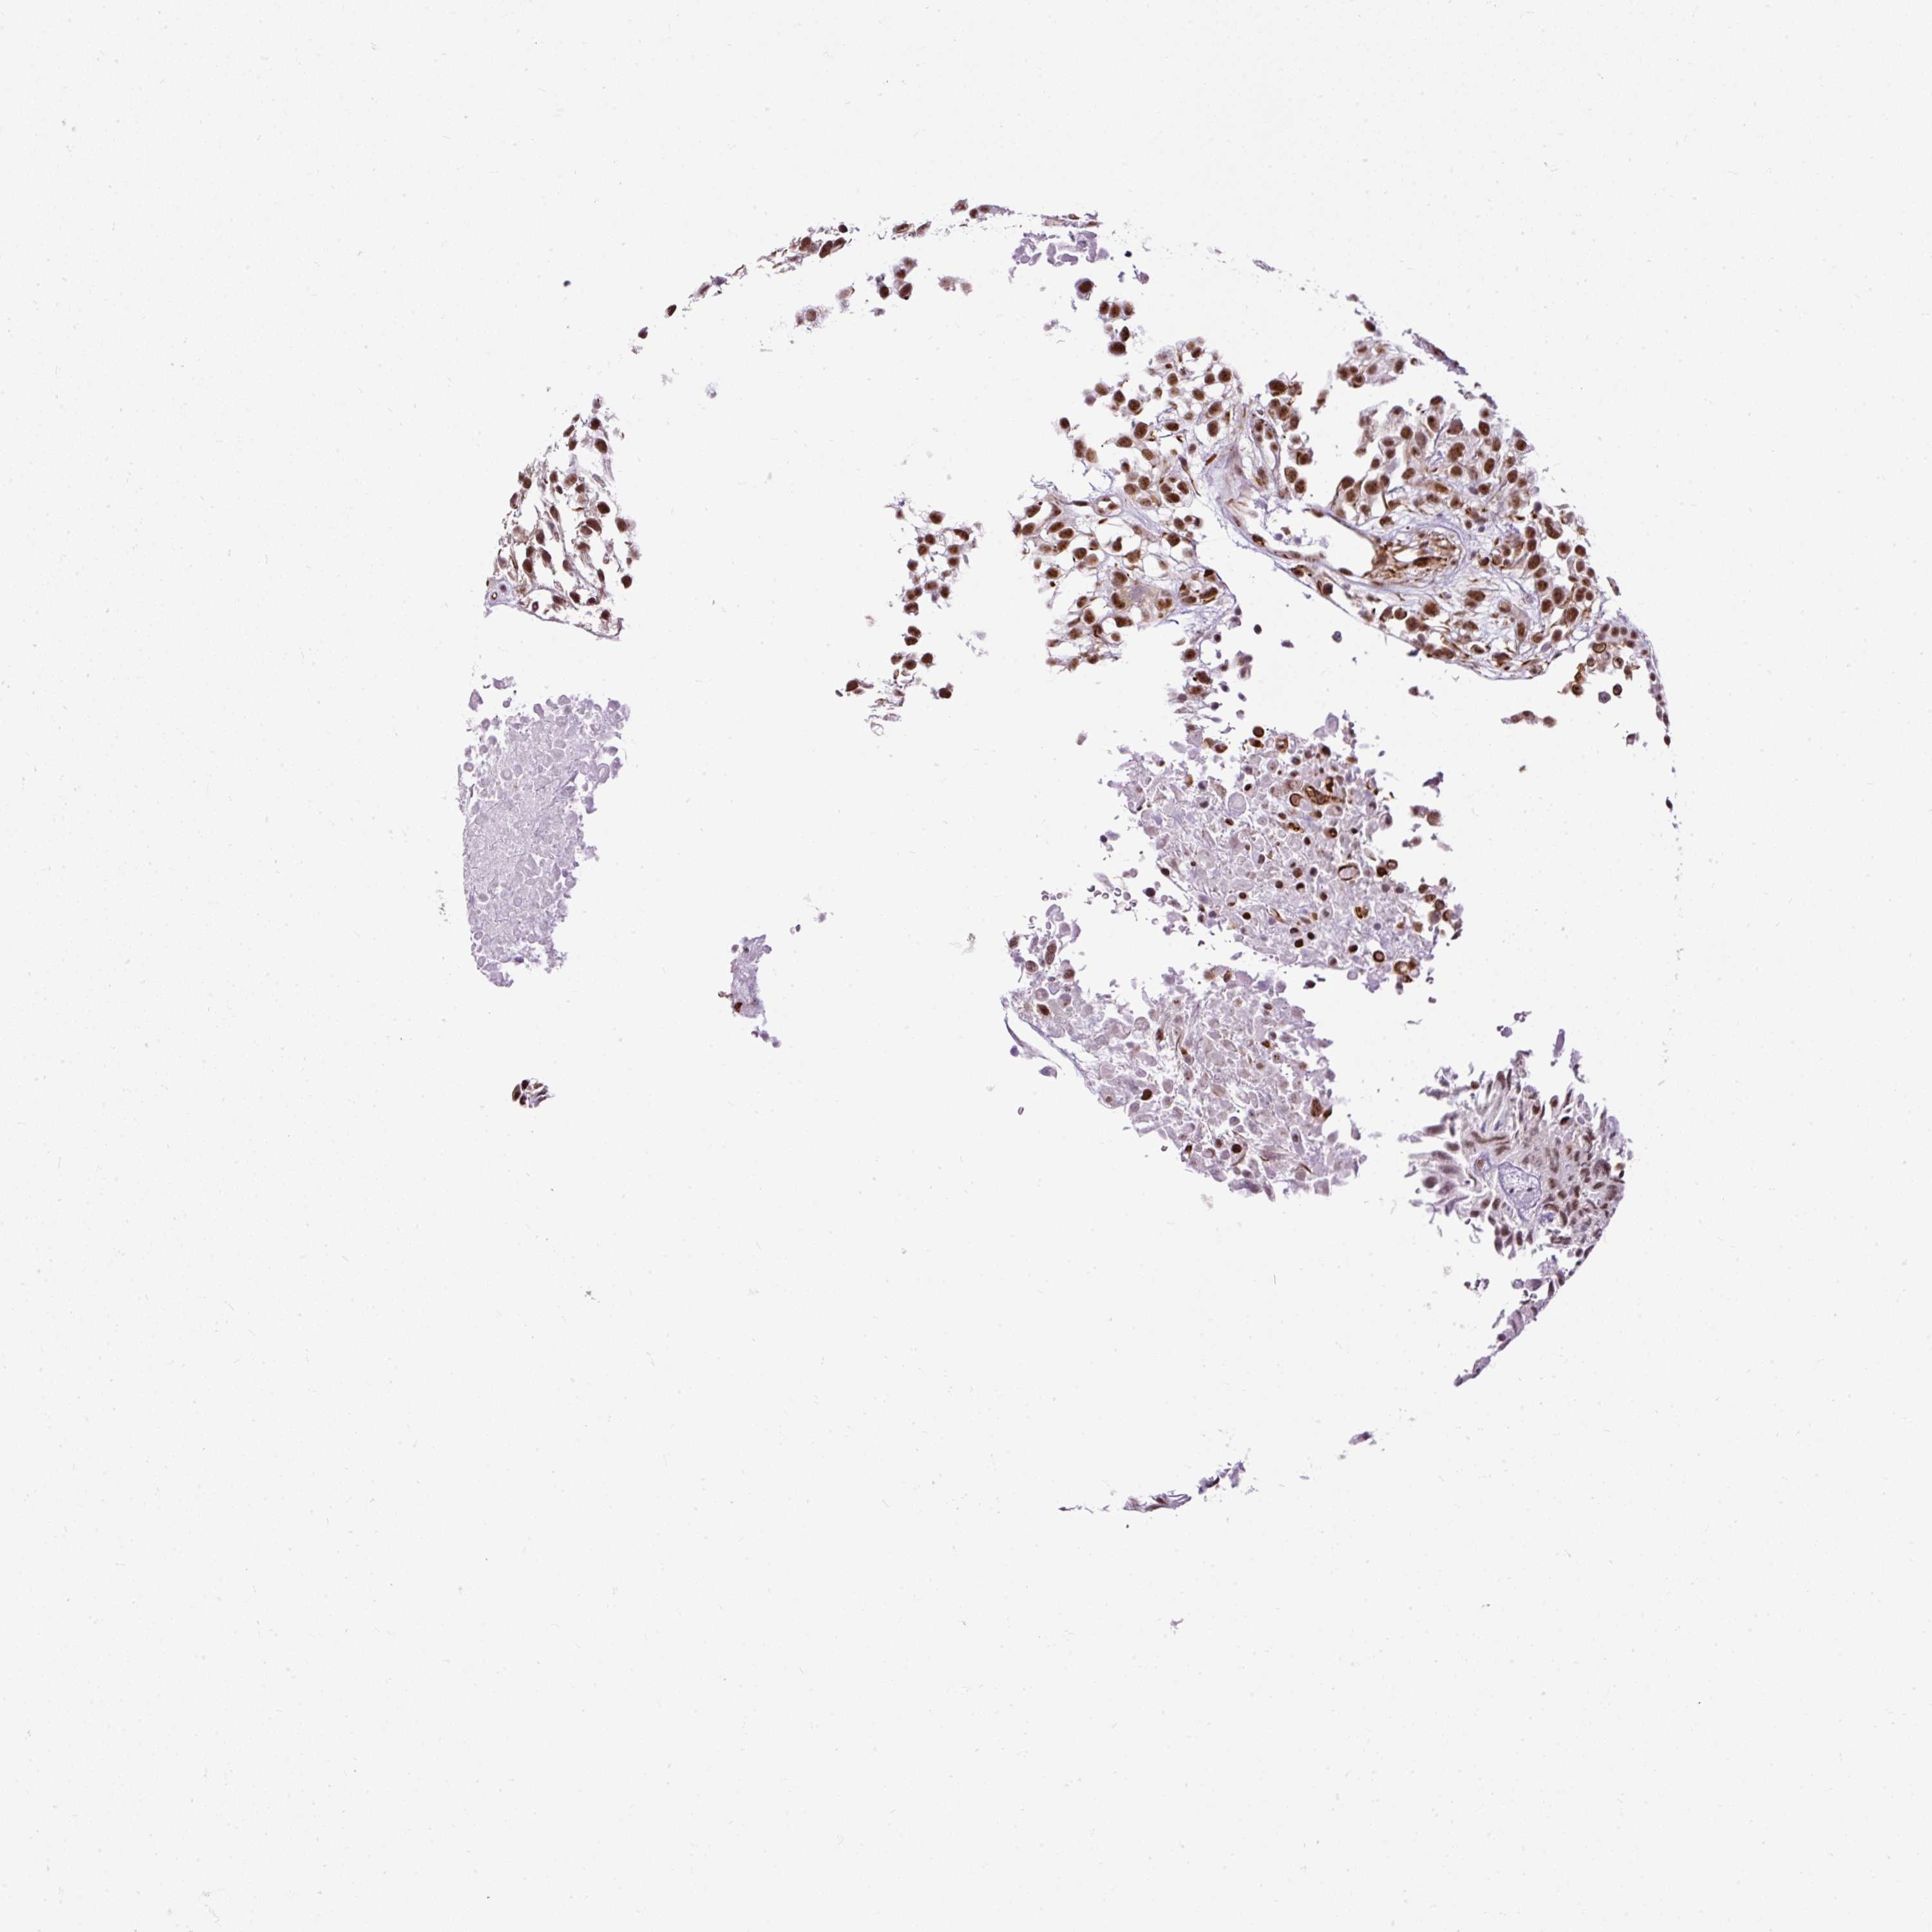

UROTHELIAL CANCER - Protein expressioni

A mouse-over function shows sample information and annotation data. Click on an image to view it in a full screen mode. Samples can be filtered based on level of antibody staining by selecting one or several of the following categories: high, medium, low and not detected. The assay and annotation is described here.

Note that samples used for immunohistochemistry by the Human Protein Atlas do not correspond to samples in the TCGA dataset.

Antibody stainingi

Antibody staining in the annotated cell types in the current human tissue is reported as not detected, low, medium, or high, based on conventional immunohistochemistry profiling in selected tissues. This score is based on the combination of the staining intensity and fraction of stained cells.

Each image is clickable and will lead to virtual microscopy that enables deeper exploration of all samples and also displays staining intensity scores, fraction scores and subcellular localization as well as patient and tissue information for each sample.

Antibody HPA045663

Antibody HPA051631

Staining

High

Medium

Low

Not detected

Intensity

Strong

Moderate

Weak

Negative

Quantity

>75%

75%-25%

<25%

None

Location

Nuclear

Cytoplasmic/membranous

Cytoplasmic/membranous,nuclear

Urothelial carcinoma, NOS